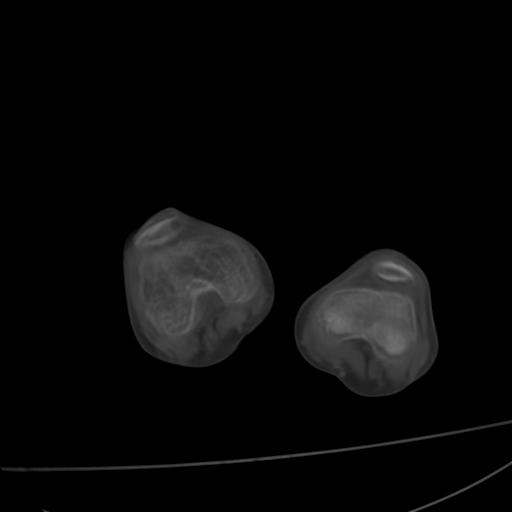

标题: PED0940:M12Y,左股骨下端酸痛畸形 [打印本页]

标题: PED0940:M12Y,左股骨下端酸痛畸形

12岁男孩,左膝关节肿痛8年,近月明显

左右无标记,大部分图像动了,提出诊断困难。

内生骨软骨瘤?

血友性关节病?